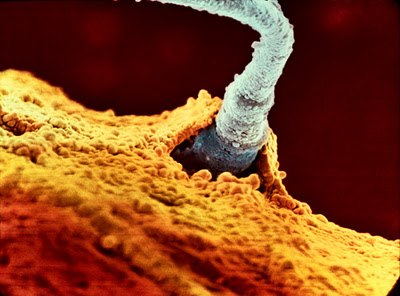

Эволюция эмбриона на фотографиях Леннарта Нильсона — шведского фотографа и ученого, пионера медицинской фотографии. Он потратил 10 лет жизни, чтобы снять на пленку эволюцию эмбриона от зачатия до рождения. Уникальные кадры с места, откуда люди делают перв10 写真